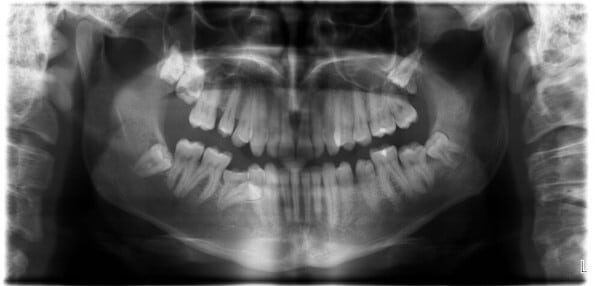

Bei der Weisheitszahnentfernung ist eine gründliche Voruntersuchung von entscheidender Bedeutung. Durch eine umfassende Voruntersuchung und die Verwendung eines dreidimensionalen DVT-Röntgenbildes kann der Zahnarzt oder Oralchirurg die genaue Lage der Weisheitszähne präzise bestimmen und den Eingriff planen. Dies minimiert das Risiko einer Verletzung des sensiblen Unterkiefernervs und verringert die Gefahr einer vorübergehenden Taubheit der Unterlippe. Während des Eingriffs erfolgt in den meisten Fällen ein Schleimhautschnitt, gefolgt von der Freilegung der Zahnkrone, der möglichen Teilung des Zahns und der Entnahme der einzelnen Zahnteile. Abschließend wird die Wunde mit Nähten verschlossen.

Das optimale Alter für die Entfernung von Weisheitszähnen liegt zwischen 16 und 25.* In dieser Lebensphase sind die Wurzeln der Weisheitszähne oftmals noch nicht vollständig ausgebildet, der Kieferknochen elastischer und der Heilungsprozess verläuft meist schneller und komplikationsärmer als in höheren Altersbereichen.

Es gibt Fälle, die ein Entfernen der Weisheitszähne sinnvoll erscheinen lassen und manchmal sogar notwendig machen. Häufig sind es nicht oder nur teilweise durchgebrochene (retinierte, teil-retinierte) und/oder schiefe (verlagerte) Weisheitszähne, die gezogen werden müssen. Insbesondere verlagerte Weisheitszähne üben häufig Druck auf die Nachbarzähne aus. Dies kann zu Zahnverschiebungen und Wurzelschädigungen führen.